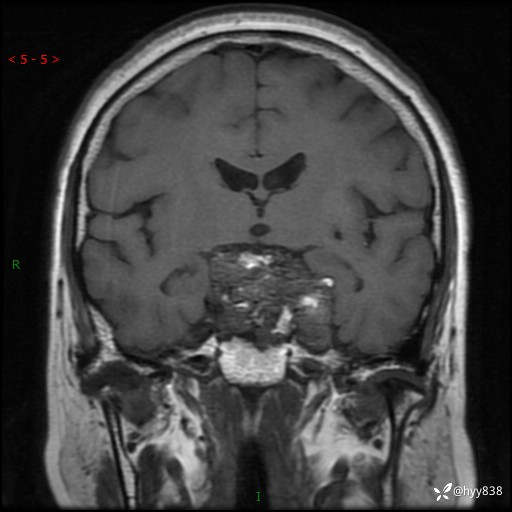

鞍区MRI平扫

T1WI cor